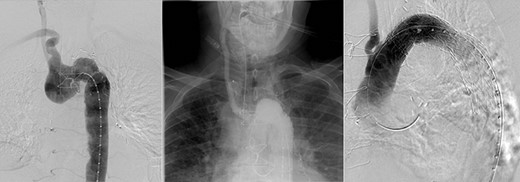

CT reconstruction illustrating a debranched left common carotid artery and subclavian artery with double coronary artery bypass graft (left internal mammary artery to left anterior descending, and saphenous vein T graft to obtuse marginal artery).

The initial procedure, performed via a median sternotomy, involved debranching the left common carotid artery (CCA) and left SCA with simultaneous double vessel CABG (left internal mammary artery to left anterior descending, and saphenous vein T graft to obtuse marginal artery) (Fig. 2). This provided a sufficient landing zone for a thoracic aortic stent graft. His post-operative recovery was complicated by atrial fibrillation, hospital acquired pneumonia and delirium requiring reintubation for severe agitation. The patient was discharged home following rehabilitation with a plan to perform the second stage of the repair as a semi-elective procedure.